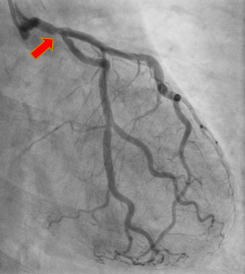

A 60 year-old infectious disease physician with history of Stage IIA Hodgkin Disease s/p radiation therapy in 1976 (age 13) presented to cardiology for new dyspnea on exertion. She had known valvular heart disease followed with serial echocardiograms. Repeat TTE completed showing now moderate to severe aortic stenosis, moderate aortic regurgitation, moderate tricuspid regurgitation, and mild to moderate mitral regurgitation. After exercise stress testing aborted due to decrease in systolic blood pressure with exertion, patient underwent cardiac catheterization and found to have moderate-severe aortic stenosis as well as hemodynamically significant ostial disease of the right coronary artery and distal left main coronary artery; classic bi-ostial coronary stenosis characteristic of RICAD. After multidisciplinary discussion with interventional cardiology, cardiothoracic surgery, and second opinion with tertiary valve center, she was referred for surgical revascularization and aortic valve replacement (AVR). Patient underwent AVR with a 23mm bioprosthetic aortic tissue valve replacement, aortic root enlargement, tricuspid valve repair with 28mm ring, and three vessel coronary artery bypass grafting.